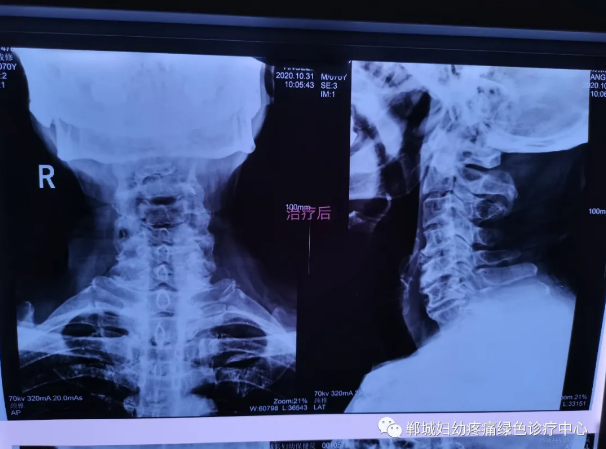

治療前李老師頸椎X線檢查影像

1個療程治療后頸椎X線檢查對比